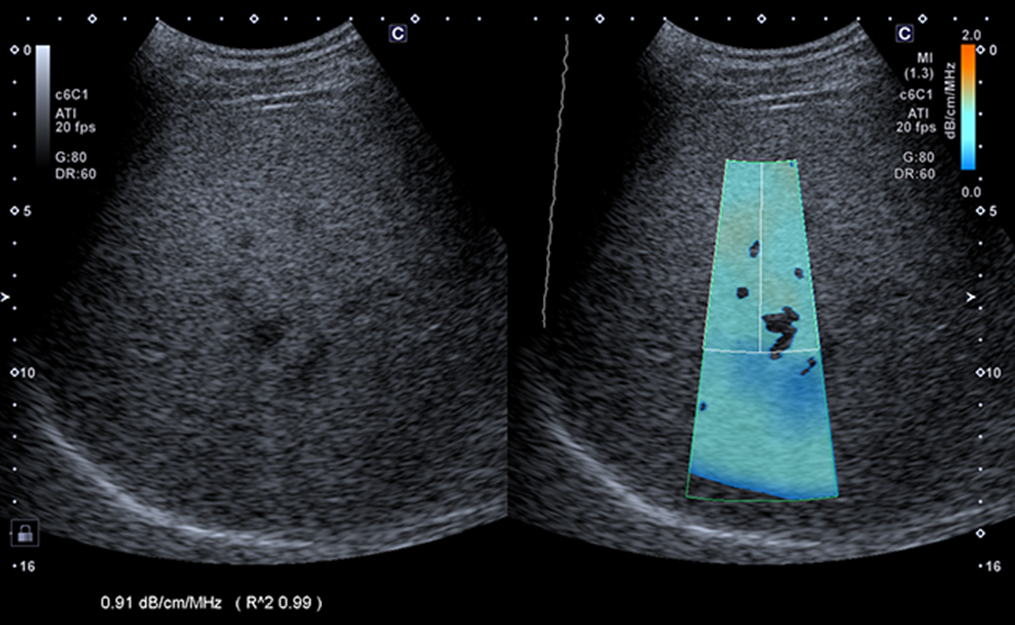

Hỗ trợ chẩn đoán bụng, gan (với ATI), túi mật, thận (ADF Color), tuyến giáp (Cine), mạch máu (Carotid CDI)…

Tích hợp Attenuation Imaging (ATI) giúp trực quan hóa hệ số suy giảm, hỗ trợ đánh giá gan nhiễm mỡ.